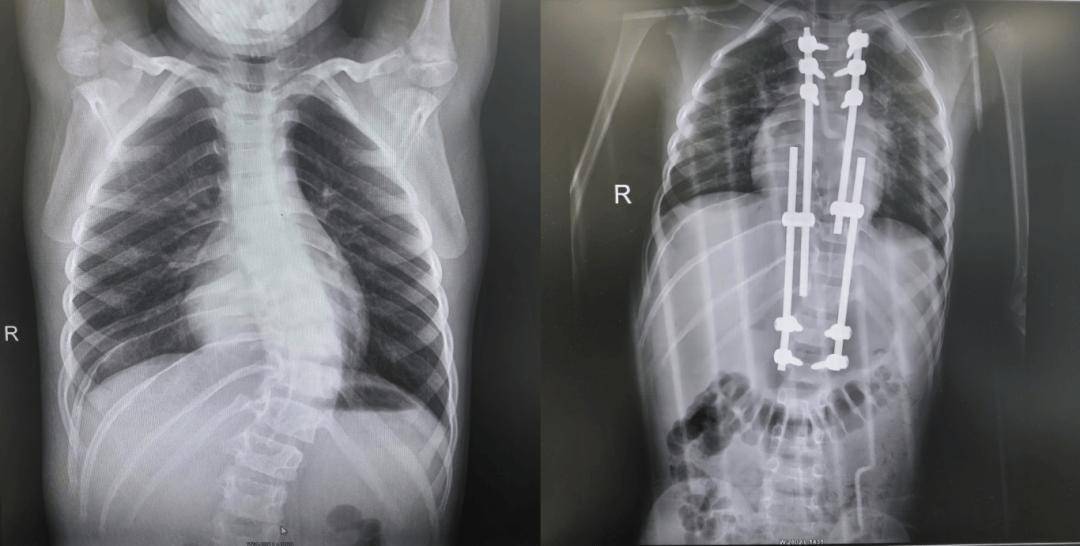

矫形手术:如果侧弯比较严重,或者支具效果有限,医生会运用最先进的器械和内固定系统,安全、精准地矫正弯曲的脊柱,并守护脊髓的安全。

△先天性脊柱侧弯畸形(半椎体畸形)术前术后